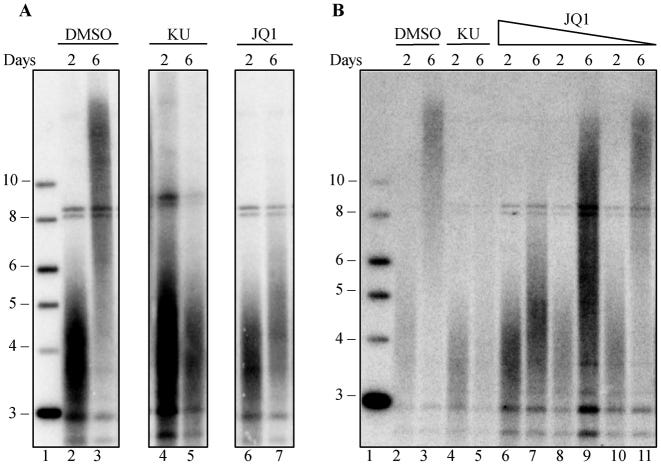

DMSO is the negative control, “KU” or KU55933 is the positive control and JQ1 is the BET inhibitor:

BRD4 translocations are linked to cancer, and BRD4 inhibition reduces cell proliferation in acute myeloid leukemia (63,64), potentially by blocking BRD4 mediated transcription of c-MYC. Our finding, that BRD4 inhibition shortens telomeres in human and mouse cells in culture, suggests that part of the mechanism by which BRD4 inhibitors block cancer cell growth (64–66) may be through telomere shortening.

Using an unbiased shRNA screen targeting known kinases, we identified bromodomain-containing protein 4 (BRD4) as a telomere length regulator. Four independent BRD4 inhibitors blocked telomere elongation, in a dose-dependent manner, in mouse cells overexpressing telomerase.

Long-term treatment with BRD4 inhibitors caused telomere shortening in both mouse and human cells, suggesting BRD4 plays a role in telomere maintenance in vivo. Telomerase enzymatic activity was not directly affected by BRD4 inhibition. BRD4 is in clinical trials for a number of cancers, but its effects on telomere maintenance have not been previously investigated.